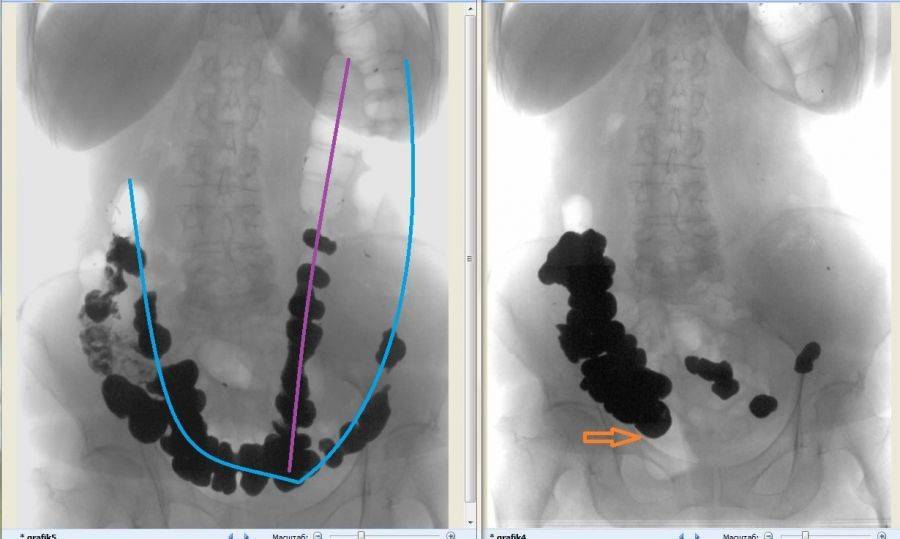

Ректальное обследование позволяет обнаружить незаполненную ампулу прямой кишки. Значит, выше имеются причины, затрудняющие прохождение кала. Рентгеновское исследование проводится путем предварительного приема внутрь бариевой взвеси или непосредственным введением контрастного вещества в кишку с клизмой (ирригоскопия).

При поступлении с питьем врач в первый день имеет возможность осмотреть пищевод, двенадцатиперстную кишку и состояние желудка. На второй день контраст должен заполнить петли толстой кишки. При рентгеноскопии выявляют: опущение кишечника (колоноптоз), задержку контраста в зоне нисходящего и сигмовидного отделов кишечника, дополнительные петли и удлинение сигмы.

Выявить удлинение сигмы у маленьких детей можно только с помощью ирригографии после введения с клизмой бариевой взвеси. Для старших детей подходит прием бария в растворе с последующей серией снимков желудка, кишечника.

Разная рентгеновская картина позволяет отличить долихосигму от похожих заболеваний